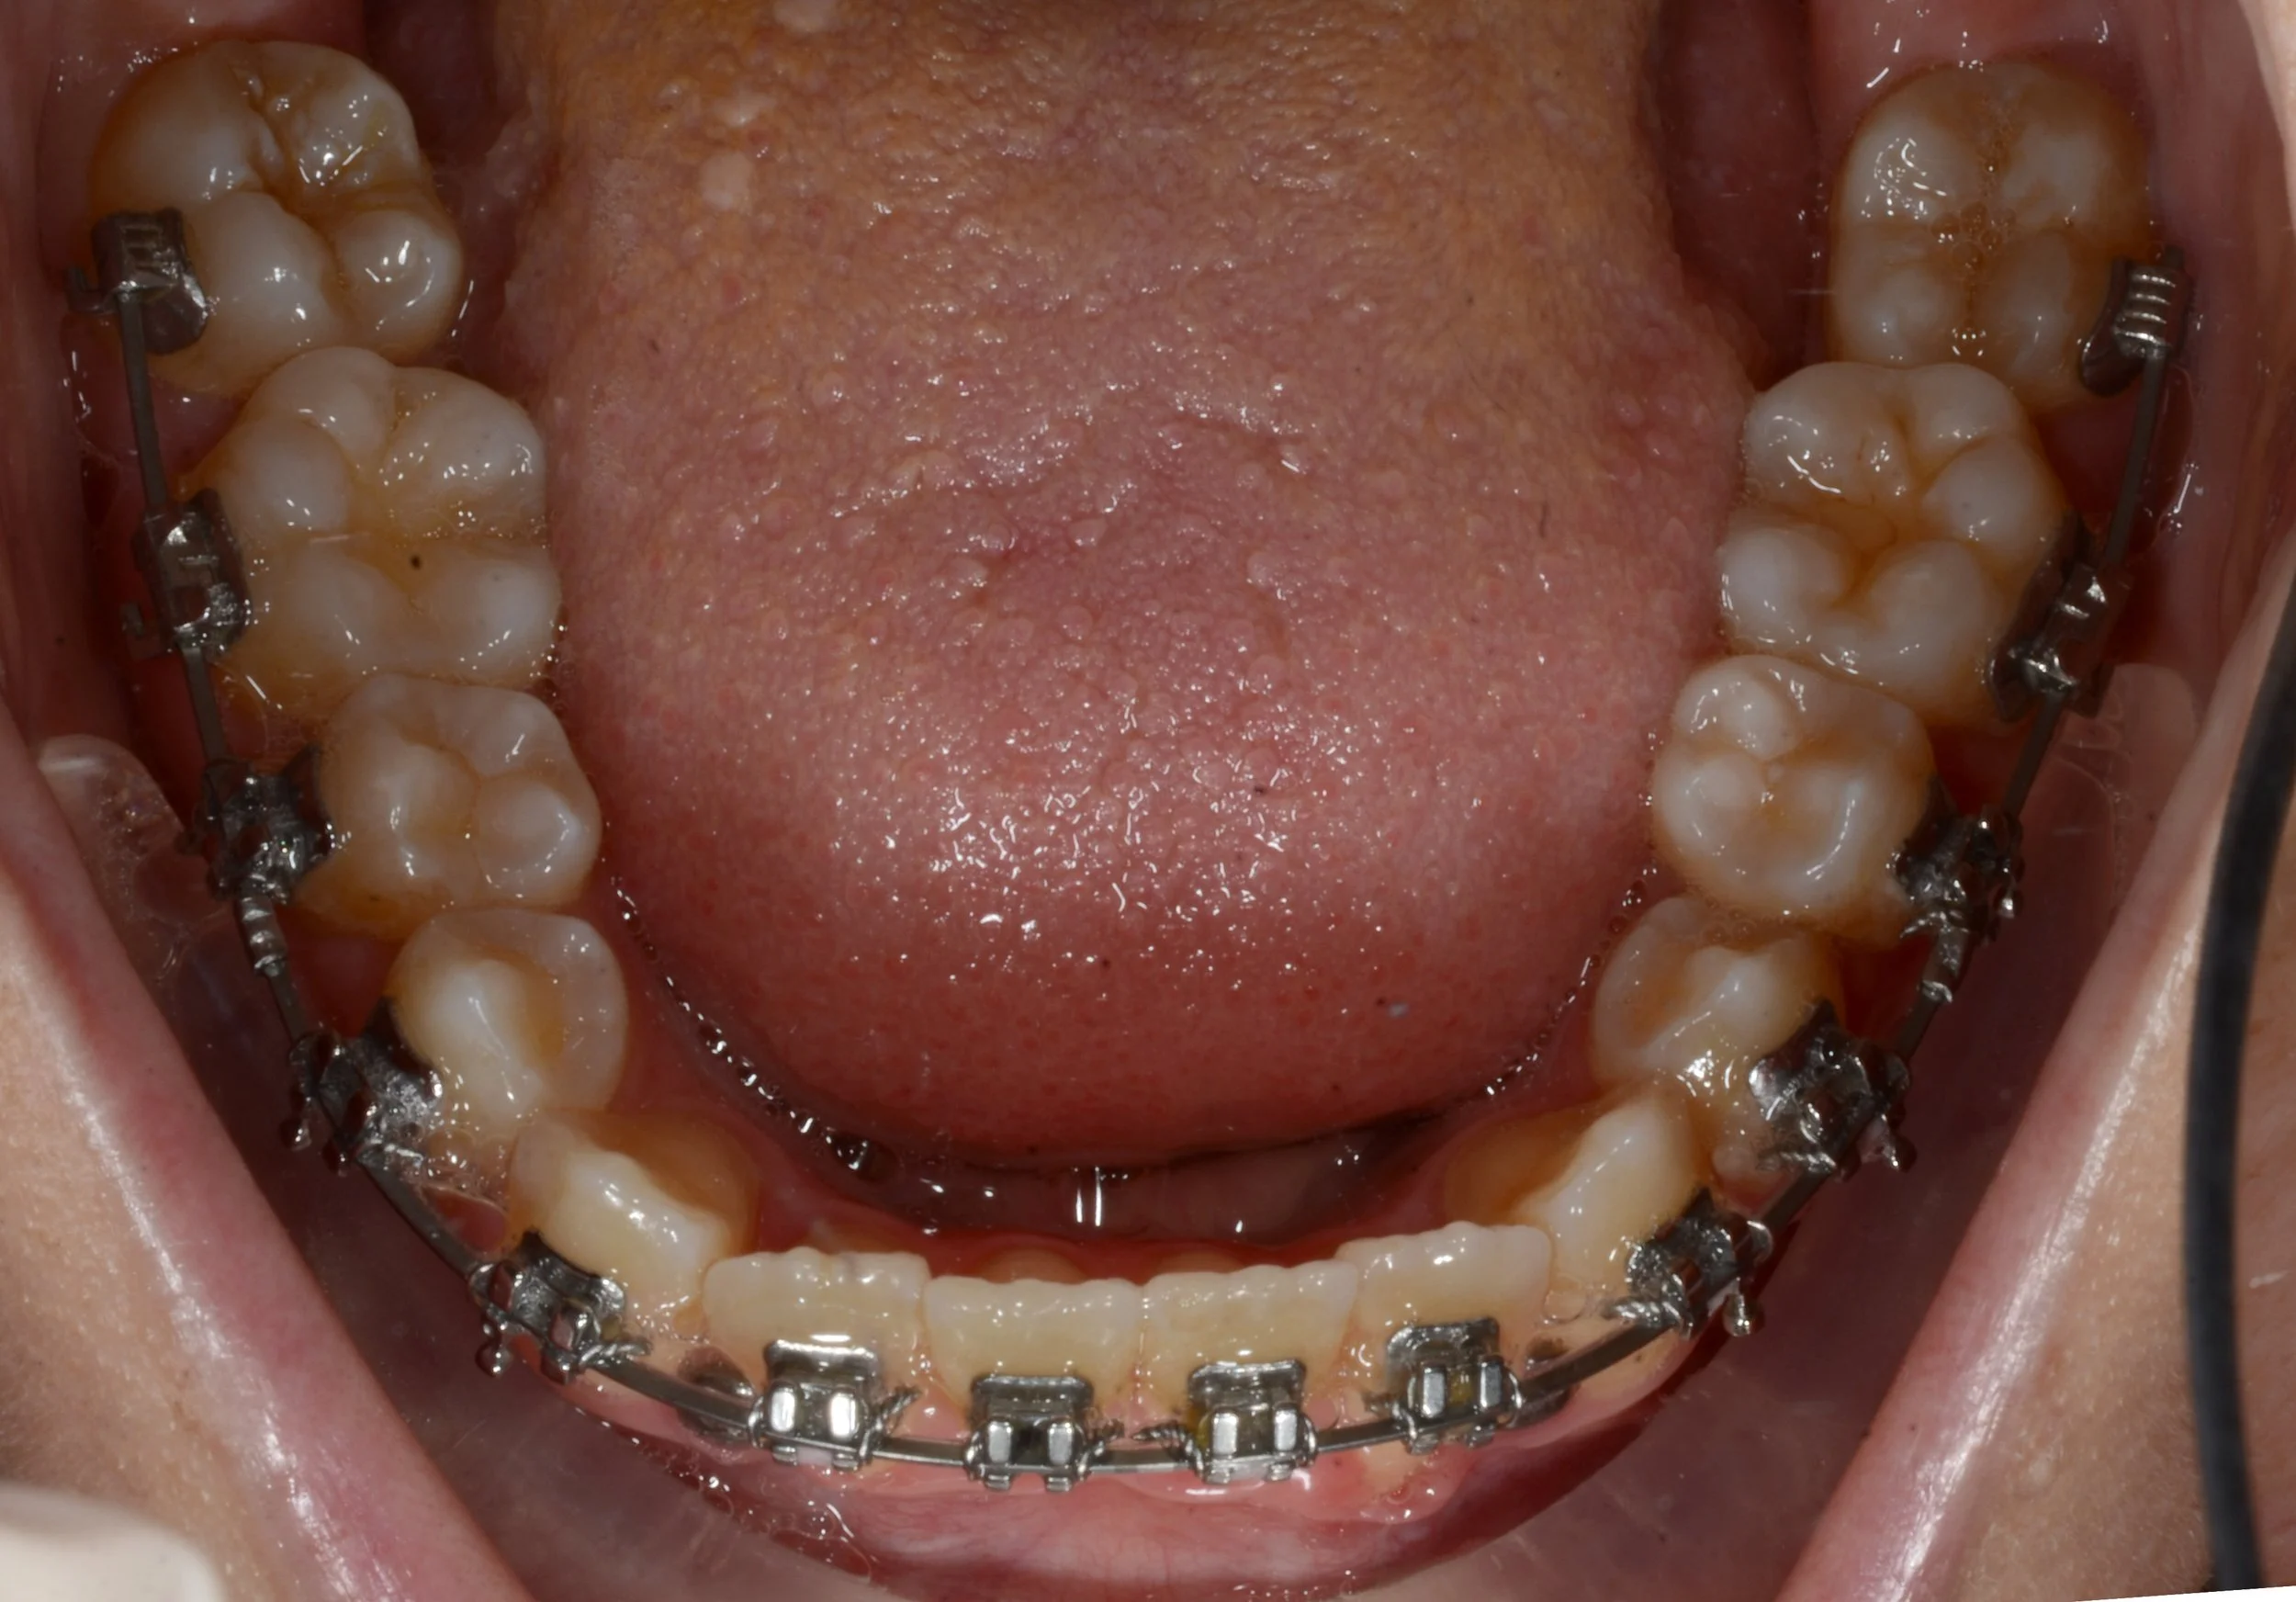

Ultimately the option she chose was to remove two teeth from the bottom in order to bring the rest of the teeth back and correct the underbite. This change would be in lieu of a skeletal correction, which would have resulted from seeing more positive changes with the bone plates or, at this point, from orthognathic surgery. “She believed it was the right path forward for her. That’s important too. Our jobs as doctors is to present everything we see and all the options and help our patients navigate them to end up with a plan they are comfortable with that will end in a result they are happy with.”- Dr. Andrew Lemchen. We referred the patient to an oral surgeon to have the teeth removed and we began to close the space.

Space closure is one of the slowest movements in orthodontics, but everyone stuck to the plan. As the spaces closed we started seeing the difference it made in her bite. The front teeth were now in a significantly better relationship, and while the relationship of the upper and lower molars was less ideal, it was still stable and healthy.

After we were able to close all of the spaces with braces, we were able to switch to aligners for the finishing and detailing stage. The detailing stage in orthodontics can be referred to as “fine tuning”. It’s where the we start making small changes in the tooth position of specific teeth to help synchronize the esthetics of a case, with the function and health of the teeth.

This patient allowed us to use attachments which are similar to brackets but match the color of the tooth to help the plastic of the aligners to get a better grip on the teeth. This gives us more control over the teeth themselves and makes these tiny movements easier and more predictably accomplished. By wearing her aligners and elastics , we were able to continue moving her lower teeth back and level her lower arch.